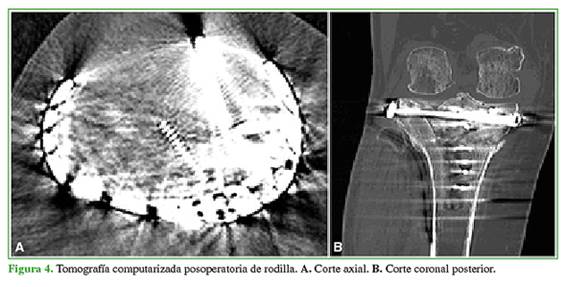

Por último, ante la inestabilidad varo-valgo, se reconstruye el ligamento colateral medial con un arpón de 4,5 mm y se corrobora la buena estabilidad clínica y radiológica posterior. Se efectúa un lavado profuso de las heridas con solución fisiológica y se cierra por planos en forma convencional con puntos separados. La tomografía del posoperatorio mostró una adecuada reducción de la fractura (Figura 4).